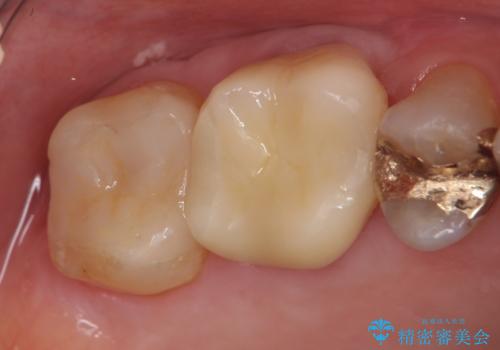

セラミックインレーついて

セラミックは強い咬合力がかかると割れてしまうリスクがあります。今回のケースでは、歯を削る量をなるべく少なくしたいとの患者様の強い希望により、セラミックインレーを作製しました。破折してしまった場合には、歯牙全体を覆うクラウンにすることを十分説明し、ご理解いただいたうえで装着しております。